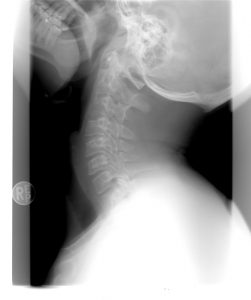

BOYUN FITIĞI BELİRTİLERİ VE TEDAVİ YÖNTEMLERİ

Fıtıklaşmış diskler omurganın herhangi bir yerinde olabilir ancak sıklıkla boyunda ve omurganın alt tarafında görülür. Boyunda görülen fıtıklara servikal herni adı verilir. Servikal diskler kafadan göğüse kadar 7 diskten oluşur.